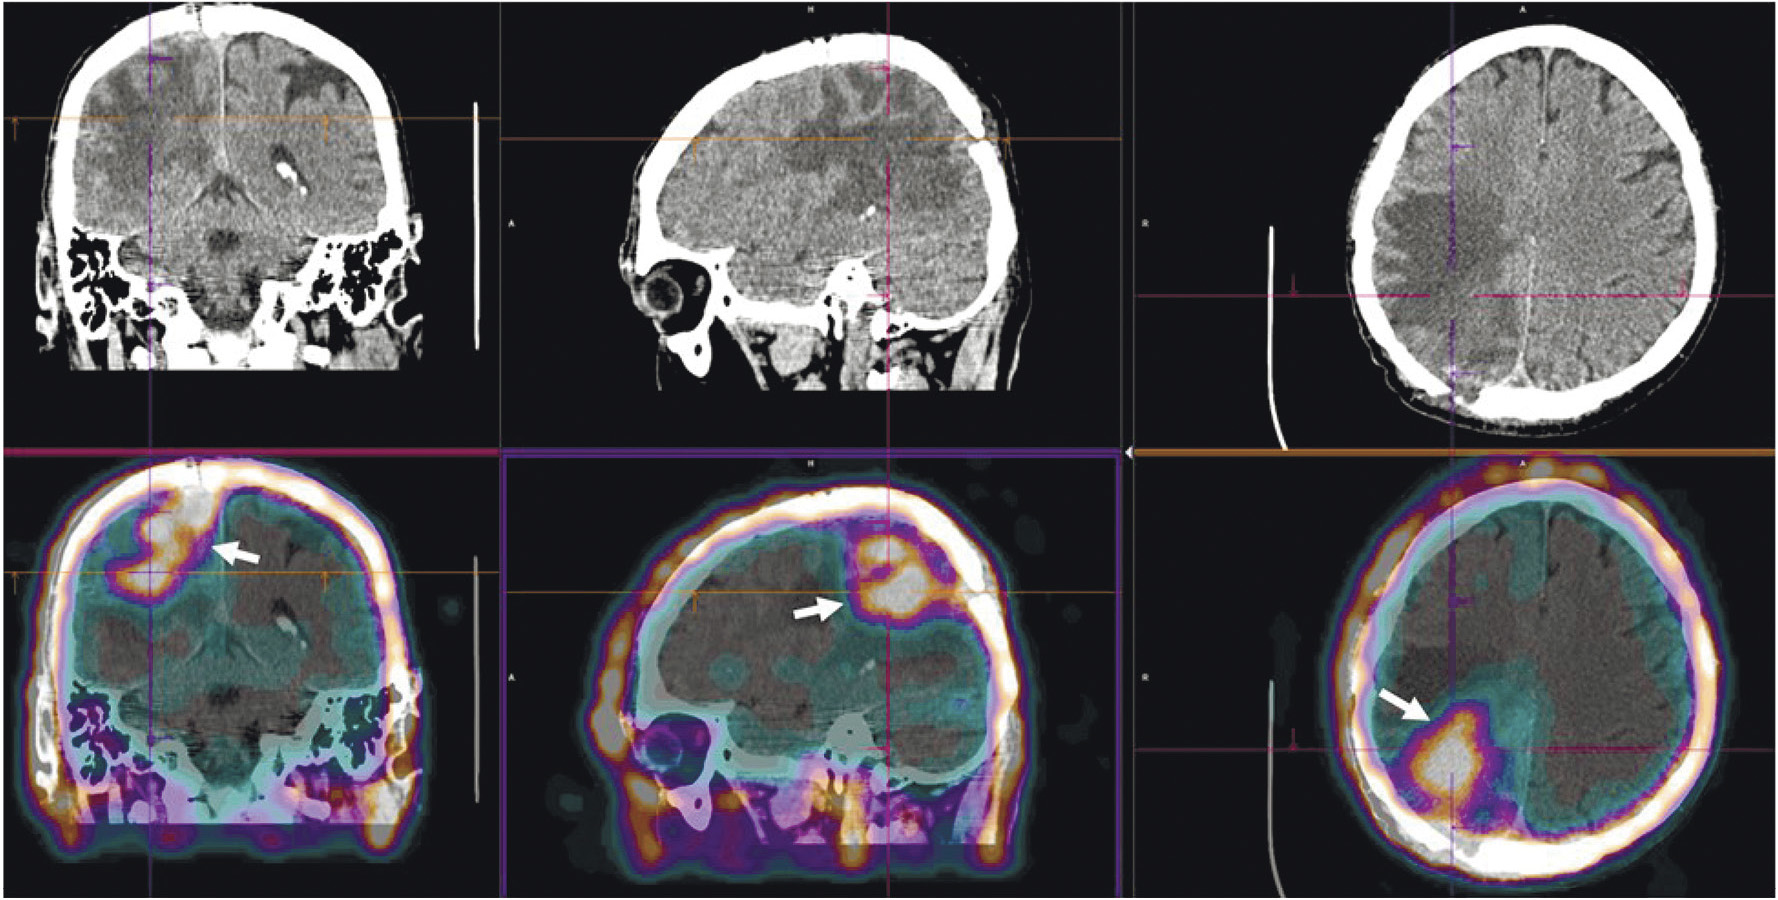

Радиофармпрепарат 99mTc-1-Тио-D-глюкоза и набор для его приготовления разработаны в НИИ онкологии Томского НИМЦ и ТПУ (“Тиоскан, 99mТс”, Россия). Неповреждённый гематоэнцефалический барьер непроницаем для данного препарата, поэтому 99mTc-1-Тио-D-глюкоза хорошо показала себя в диагностике опухолей головного мозга (рис. 7) [43]. Кроме того, ОФЭКТ/КТ с 99mTc-1-Тио-D-глюкозой рекомендована для стадирования и прогноза результатов лечения лимфопролиферативных заболеваний (рис. 8) [44, 45].

Рис. 7. ОФЭКТ/КТ с 99mTc-1-Тио-D-глюкозой пациента с рецидивом глиобластомы. Стрелками обозначено накопление РФЛП в опухоли

Рис. 8. ОФЭКТ/КТ с 99mTc-1-Тио-D-глюкозой пациентки с лимфомой Ходжкина. Стрелками обозначено накопление РФЛП в лимфатических узлах правой аксиллярной области

Имеющиеся в арсенале радиологов радиофармацевтические лекарственные препараты для визуализации СЛУ отличаются невысокой аккумуляцией (1.5–2% от введённой дозы). Поэтому в НИИ онкологии Томского НИМЦ и ТПУ был разработан оригинальный РФЛП на основе гамма-оксида алюминия “Сентискан, 99mТс” с высокими (около 12% от введённой дозы РФЛП) уровнем накопления в сторожевых лимфатических узлах [46]. Набор для его приготовления получил регистрационное удостоверение. Клинические испытания показали оптимальную фармакокинетику этого индикатора для интраоперационного выявления СЛУ и высокую эффективность при хирургических вмешательствах в случае рака шейки матки, рака эндометрия и злокачественных новообразований молочных желёз (рис. 9) [47, 48].

Рис. 9. ОФЭКТ/КТ пациентки с раком правой молочной железы после паратуморального введения РФЛП “Сентискан, 99mТс”